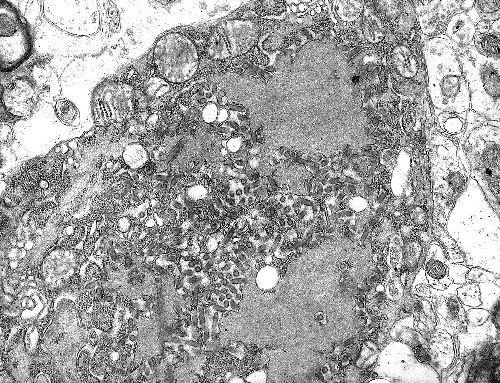

diem danh nhung virus dang so tren trai dat hinh 3

Virus SARS-CoV-2. Ảnh: NIAID-RML

Kể từ khi xuất hiện, virus SARS-CoV-2 gây nên đại dịch Covid-19 đã khiến hơn 2,6 triệu người mắc bệnh và gần 185.000 người tử vong tính tới ngày 23/4, làm đảo lộn cuộc sống trên toàn thế giới.